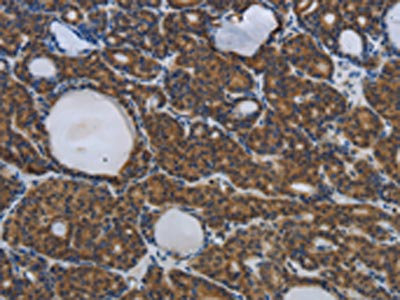

The image on the left is immunohistochemistry of paraffin-embedded Human thyroid cancer tissue using CSB-PA919263(SPAG4 Antibody) at dilution 1/25, on the right is treated with synthetic peptide. (Original magnification: ×200)